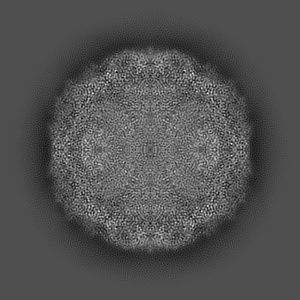

Cryo-EM structure of enterovirus A71 mature virion

Single-particle3.07 Å